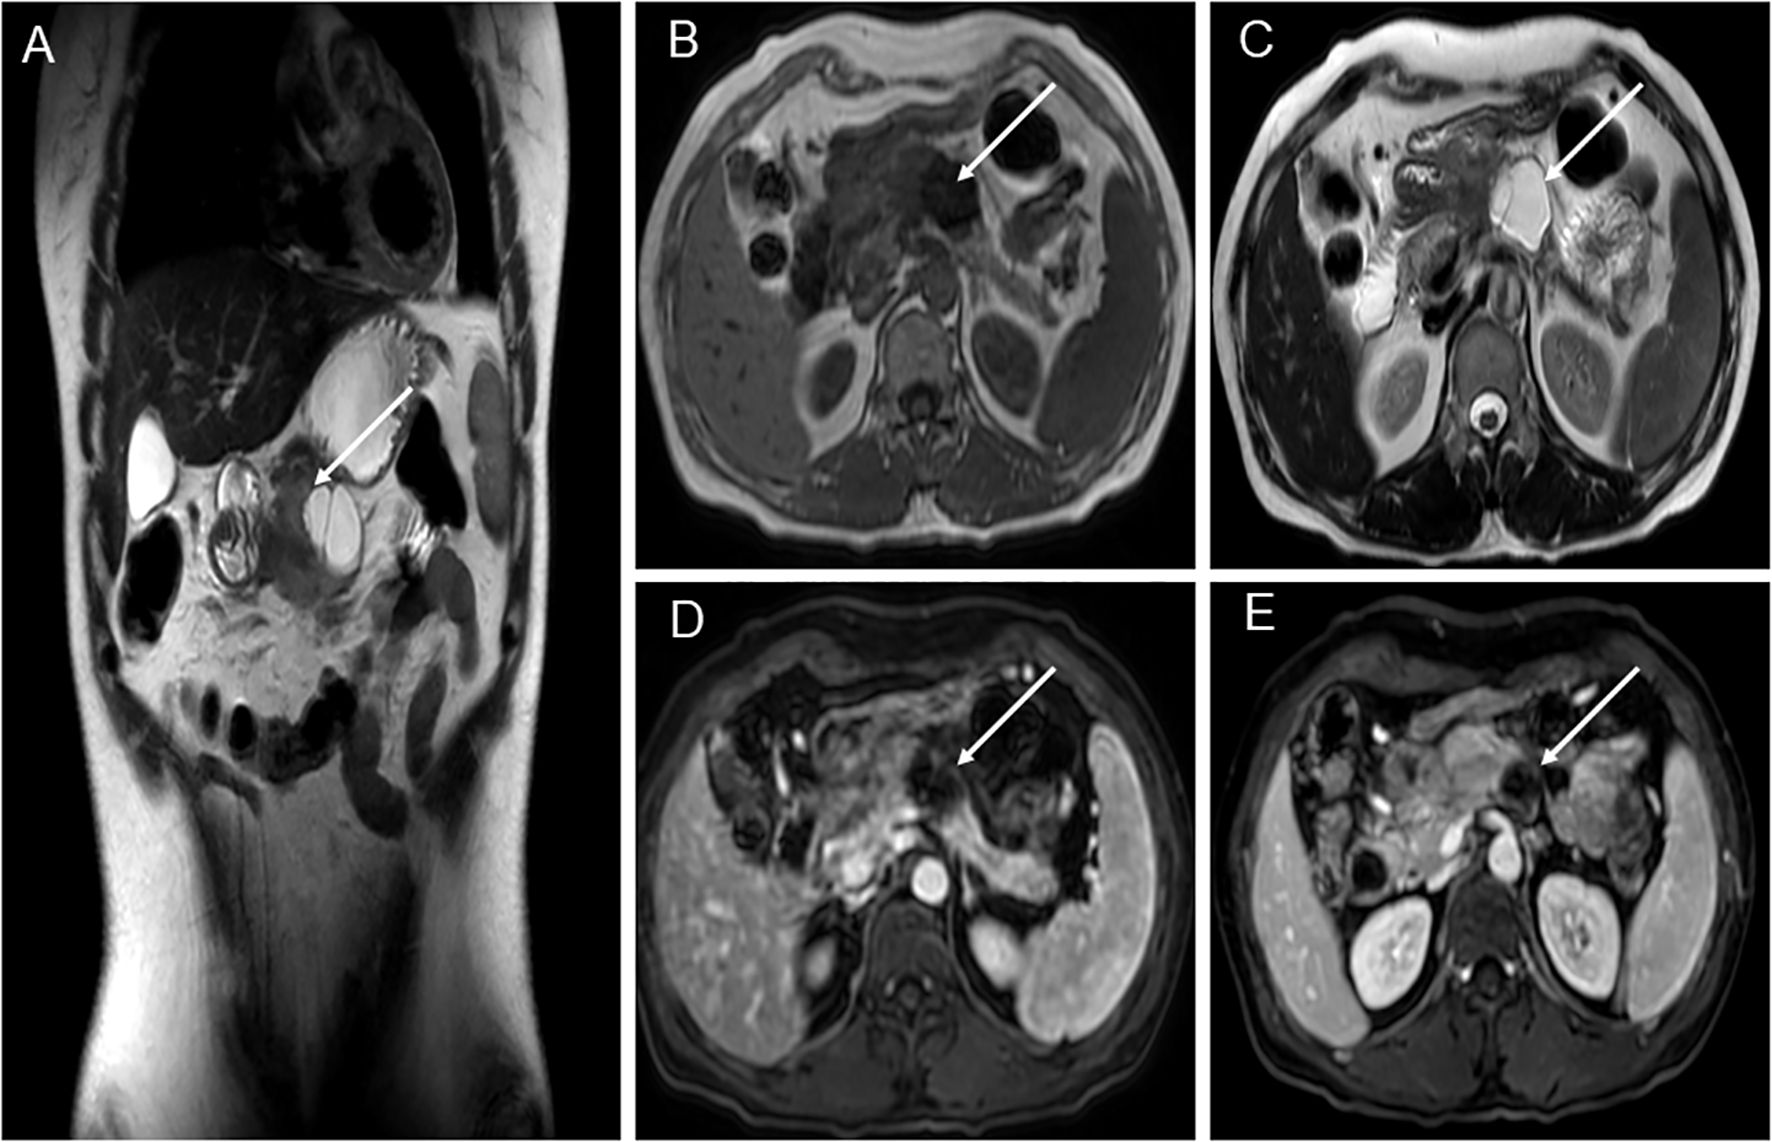

A 39-year-old woman presented with left upper abdominal pain for 20 days and was admitted to the hospital. The pain is persistent and dull in the epigastric region. She described the pain as dull, severe, and non-radiating. The pain was heavier at night than during the day and was related to body position. The bent-knee and bent-hip positions could reduce the pain. It was frequently accompanied by nausea and vomiting, and the vomit was gastric contents and bile. An abdominal CT scan and MRI performed at another hospital had revealed a space-occupying lesion in the pancreas. There was no relevant medical or family history, and the patient had no history of smoking or alcohol consumption. On physical examination, the patient presented with a good general condition and no abnormalities of note. Laboratory tests showed (reference ranges are given in square brackets) the following: glutamyl transferase (72 U/L, reference range 7–32 U/L); lipase (62 U/L, reference range <60 U/L); amylase (31 U/L, reference range 35–135 U/L); and alkaline phosphoric acid (234 U/L, reference range 45–125 U/L). The tumor marker showed no obvious abnormality (CEA, CA199, AFP, and CA125 are normal). The ultrasonography showed a mixed cystic-solid echogenic structure between the body of the pancreas and the posterior wall of the stomach (Figure 1). The mass size was approximately 5.9 cm × 4.1 cm × 3.2 cm with a well-defined margin. The mass was observed to be internally separated by multiple compartments, but there was no obvious relationship with the stomach. A small amount of blood flow signal could be seen. Endoscopic ultrasonography showed a large cystic solid mass in the gastric sinus, posterior to the gastric wall, and at the neck of the pancreas (Figure 2). It was approximately 5.2 × 3.4 cm in size; the border lacked clear boundaries; the solid area was predominant at the wall of the gastric antrum; and the gastric body was dominant behind the cystic region. Multiple septations could be seen within the lesion. The CT plain scan and enhancement showed a mass of flaky cystic-solid mixed-density shadows in the pancreas and gastric hiatus; the lesion was indistinctly distinguished from the gastric wall and the body of the pancreas, and it measured about 6.93 × 3.87 cm. Enhancement scan of the solid portion of the inhomogeneous enhancement, which was considered the possibility of a gastric mesenchymal tumor. MRI showed the lesion with slightly longer T1 and T2 signals, slightly higher signals on DWI, and slightly lower signals on ADC; mild-moderate enhancement; unclear borders; and approximately 3.6 cm × 3.6 cm × 2.8 cm in size; the lesion was poorly demarcated from the neck of the pancreas (Figure 3). To prevent iatrogenic tumor cell dissemination, we also considered the patient’s preference for surgery. Taking all these factors into consideration, we did not perform an endoscopic ultrasound.

Figure 3. MRI of patient before operation. (A) Pancreatic-gastric space; solid and cystic lesions anterior-inferior to the pancreas. Cystic lesions showed internal septa, measuring approximately 3.6 cm × 3.6 cm × 2.8 cm, with indistinct borders to the gastric antrum and pancreas. (B) Solid lesions showed slightly lower T1 signal intensity, while cystic lesions exhibited low T1 signal intensity. (C) Solid lesions showed slightly elevated T2 signals, while cystic lesions exhibited high T2 signals. (D) T1-weighted sequence. (E) Mild-moderate enhancement after contrast administration, measuring approximately 3.6 cm × 3.6 cm × 2.8 cm, with indistinct borders at the gastric antrum and pancreas.